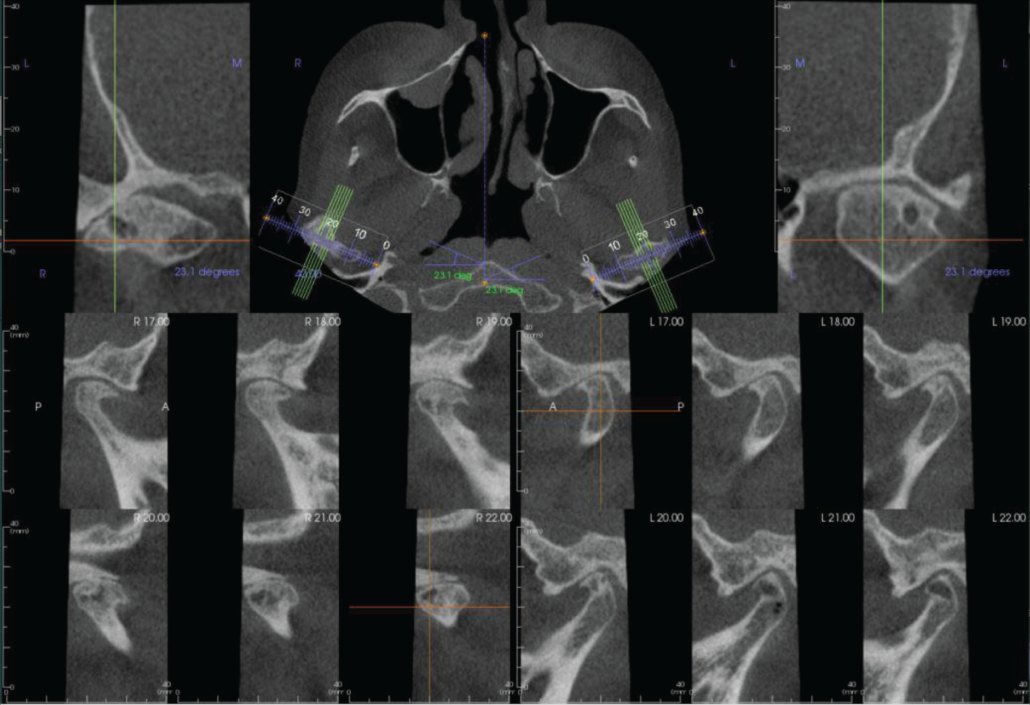

Both TMJs have severe degenerative joint disease with condylar osteophytes and flattening of the right glenoid fossa. The left condylar head has an Ely’s cyst (also called a subcortical or subchondral cyst).

Bilateral parasagittal sections of the TMJs. Both joints have severe degenerative joint disease with condylar osteophytes and flattening of the right glenoid fossa. The left condylar head has an Ely’s cyst.